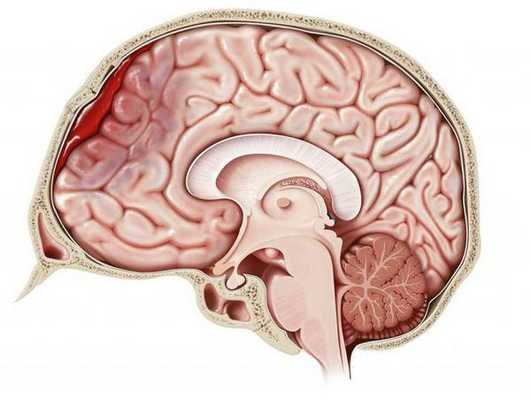

Решающими методами в диагностике субдуральной гематомы являются КТ и МРТ головного мозга. В диагностике острых гематом предпочтение отдается КТ головного мозга, которая в таких случаях выявляет однородную зону повышенной плотности, имеющую серповидную форму. С течением времени происходит разуплотнение гематомы и распад кровяных пигментов, в связи с чем через 1-6 нед. она перестает отличается по плотности от окружающих тканей. В подобной ситуации диагноз основывается на смещении латеральный отделов мозга в медиальном направлении и признаках сдавления бокового желудочка.

При проведении МРТ может наблюдаться пониженная контрастность зоны острой гематомы; хронические субдуральные гематомы, как правило, отличаются гиперинтенсивностью в Т2 режиме. В затруднительных случаях помогает МРТ с контрастированием. Интенсивное накопление контраста капсулой гематомы позволяет дифференцировать ее от арахноидальной кисты или субдуральной гигромы.